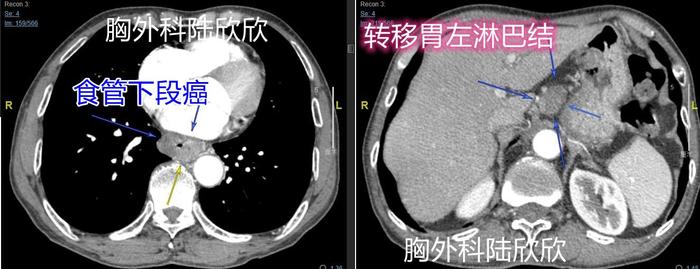

2021年南京疫情过后,一个同事带他的舅舅来住院。病人,男性,67 岁。吞咽梗阻已经有2个多月了。只能喝粥,不能吃干饭。体重下降了1kg,只有88斤。这人太瘦了。我记得自己初中毕业时身高1米73,体重108斤,非常瘦。我能记得住当时的体重,是因为108 这个数字正好和水浒108将对应。这个病人身高1米60,体重88斤,比我当年还要瘦,几乎没有皮下脂肪。胃镜是在江苏省中西医结合医院做的,报告如下:距门齿35cm见食管隆起性病灶,贲门光滑,胃、十二指肠因进镜阻塞感明显,食管出血,停止进镜。病理示:鳞状上皮高级别上皮内瘤变。就是说,胃镜穿过食管癌中间狭窄的缝隙,想观察下面的胃时,由于缝隙较小,胃镜镜身与肿瘤摩擦导致出血,最后胃镜检查只好提前终止。术前诊断为食管癌伴胃左淋巴结转移。

上图为图1。左边的图,心脏和降主动脉间可见食管下段癌较大,三个箭头指示。肿瘤中间的缝很狭窄,做胃镜检查时挤得慌,所以当时肿瘤有点出血。上面右边的图,肝脏和胃间可见一枚胃左淋巴结肿大,大约23×18mm,四个箭头指示。这个淋巴结是食管癌转移后肿大的